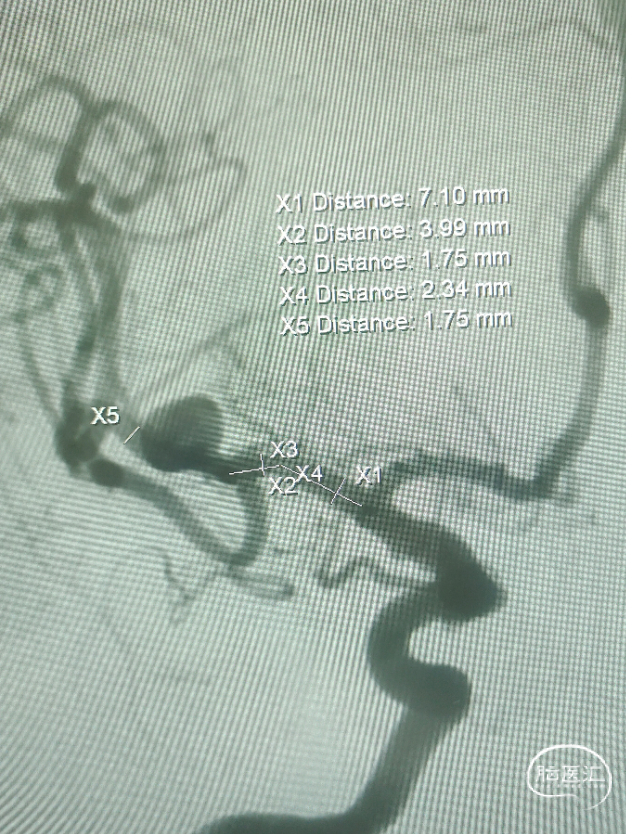

3D造影及测量:

2、术中血管的准确测量、选择合适FD,避免覆盖后交通等。

支架系统:血流导向装置Lattice 4.7mm*15mm

1、两次造影测量差异大,术中根据中间导管对比测量选择使用4.7mm*15mm。

2、原位释放,推挤力量偏大时,支架前端部分会覆盖后交通;转弯处推拉,近端部分打开后回拉打开,减张释放,自膨式机械球囊按摩过管。